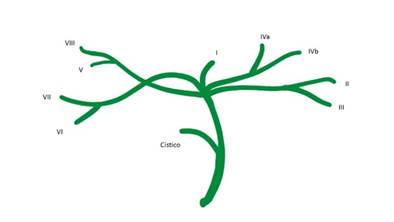

La anatomía biliar es modal (normal) entre el 53-58 % de la población1 . La anomalía más frecuente se vincula con el abocamiento del conducto lateral posterior derecho en el hepático entre el 11%-15,6 %. 1-2 . Más allá de ello, se conocen múltiples variaciones, bien estudiadas y clasificadas por diversos autores, producto de la compleja embriología hepato-bilio-pancreática . Entre ellas, la denominada confluencia escalonada ("convergence étagée","selved confluence"), que admite muy diversos patrones de hilio hepático biliar 3. En menos de un 5% de los casos se puede observar la llegada por separado de todos los canalículos segmentarios independientes para formar un hilio sin “hepáticos”(Fig.1), como en la imagen hallada en el curso de una colangiografia intraoperatoria (Fig. 2), realizada durante una colecistectomía de urgencia.

Fig. 1 Muestra en forma esquemática, la ausencia de confluente biliar superior, debido a la falta de unión, en la cara visceral del hígado- de los hepáticos derechos e izquierdo. El colédoco se origina de la confluencia independiente de todos los conductos segmentarios.